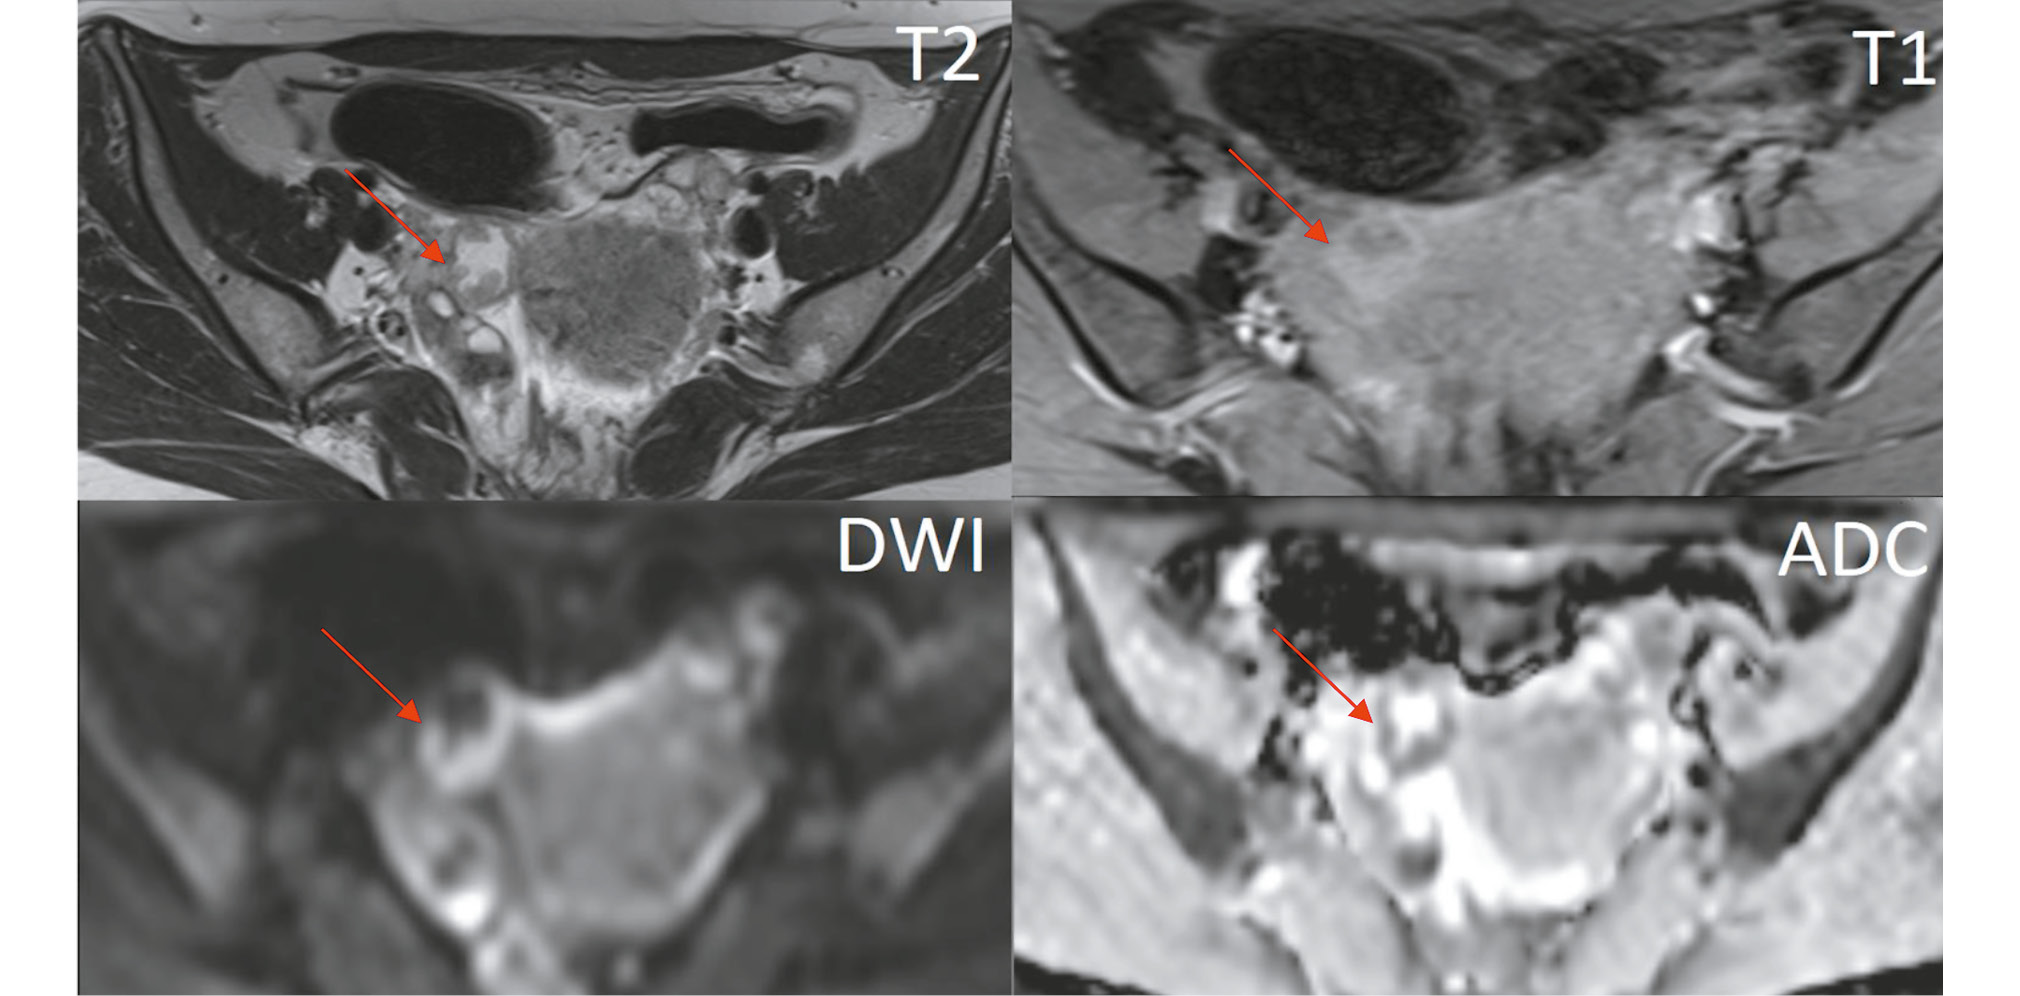

A tubular structure with high fluid signal intensity and an irregular lumen, measuring up to 17 mm, was located adjacent to the anterior and outer contours of the right ovary. This structure had multiple hypervascular solid nodules on the walls and showed signs of restricted diffusion in the DWI sequence (Fig. 4). A smaller structure with similar MRI characteristics was observed on the left (Fig. 5).

Fig. 4. Pelvic magnetic resonance imaging (axial view). The right fallopian tube contains fluid and solid nodules, with signs of restricted diffusion on DWI mode (red arrow).

- Oblong or tubular lesions in the adnexal area, often with relatively uniform fluid signal intensity (low on T1WI and high on T2WI). In our case, the lesion contained several solid foci on the walls, clearly visible against the backdrop of the distended fallopian tube. These solid foci showed restricted diffusion on DWI/ADC and early contrast uptake in the dynamic contrast-enhanced sequence.

- Fluid in the fallopian tubes (hydrosalpinx): This condition results from tumor secretions that block the fallopian tube, causing colic-like pelvic pain due to stretching. The contents of the hydrosalpinx can vary, leading to different MRI signals. In our case, the fallopian tubes were distended with serous fluid, although a hemorrhagic component due to recurrent bleeding is also possible.